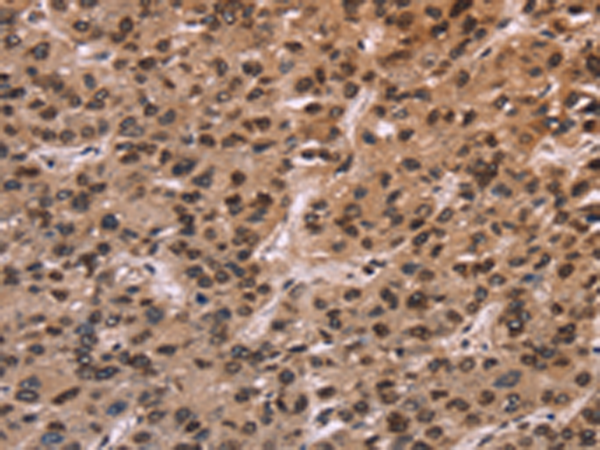

分类: 科研抗体货号: P07407别名: FLA10; KLP-20应用: WB,IHC反应种属: Human, Mouse